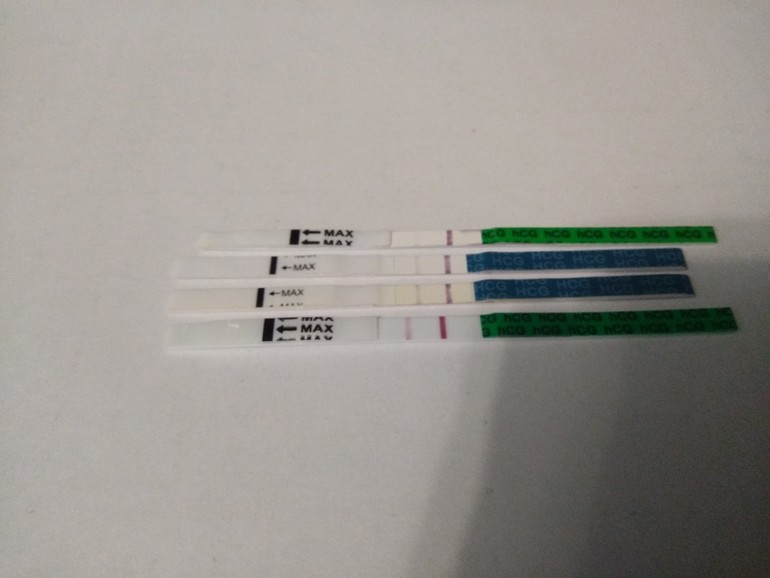

Канун нового года. Упаковка подарков родственникам, родителям и друзьям. Это такая замечательная традиция. Вот маме новая мультиварка, а вот отчиму новый свитер и электронная сигарета, он так хотел бросить курить. Сестре новое постельное белье и часы, как она просила. Мы много копили, чтобы всем все понравилось. Даже улыбаемся, довольны собой. Накрываю на стол и… меня тошнит. Наверное, моя болячка дает о себе знать. С грустью думаю о том, как буду снова делать уколы и пить антибиотики. Снова тошнит, а потом даже немного рвет. На стене висит календарь, с удивлением замечаю, что у меня красные дни календаря перенеслись на пару дней. Задержка. Точно от лечения. Но иду в дежурную аптеку за пачкой тестов, которых к тому моменту дома не было уже полгода. Сонная аптекарша просовывает один тест, больше и не надо, все равно ничего нет. Иду домой, очень холодно. Начинает ныть левый бок. Воспоминания нахлынули с новой силой. Неужели…внематочная? Гоню от себя дурные мысли, но слезы уже текут по щекам. Надеюсь, малыш, ты попал к лучшим родителям, тогда я не смогла тебя родить. Я почти тебя отпустила… Дома пахло маминым пирогом с мясом. Приехали. Отложив тест в сторону помогаю дальше накрывать на стол.

Новый год. Все пьют шампанское. А мне не хочется. Жую пять минут пол бутерброда с икрой и думаю, думаю, думаю. Что я хочу в новом году? Опять приходит боль в левом боку, немного скрючиваюсь. Плохо, это очень плохо. Больницы нормально не работают, скорая ездит по пьяным. Сделают полостную и домой отправят? Точно… купила же тест.

Несколько минут после. Сижу на туалете и реву. Слезы капают на пол. Яркие две полоски с теста гадко улыбаются мне в лицо. Внематочная, сволочь!